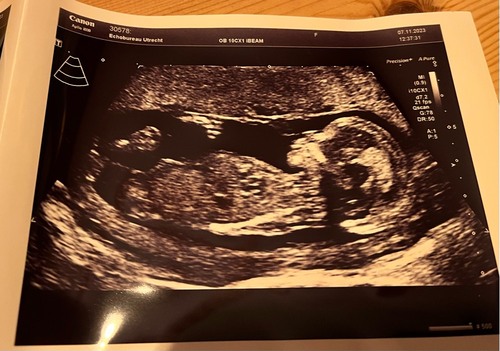

Jeetje wat een onwijs fijne uitleg, hiermee heb ik nu zelf de nub kunnen vinden uit mijn filmpje van de echo van laatst. Alleen ik twijfel heel erg wat het word?

13+6 dagen, dit was alleen het beste shot die ik kon krijgen, helaas zonder blaas en ruggengraat niet geheel mooi erop.